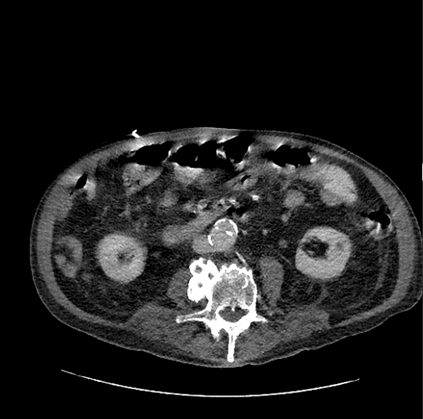

In this study, we aim to initiate the development of Radiology Foundation Model, termed as RadFM.We consider the construction of foundational models from the perspectives of data, model design, and evaluation thoroughly. Our contribution can be concluded as follows: (i), we construct a large-scale Medical Multi-modal Dataset, MedMD, consisting of 16M 2D and 3D medical scans. To the best of our knowledge, this is the first multi-modal dataset containing 3D medical scans. (ii), We propose an architecture that enables visually conditioned generative pre-training, allowing for the integration of text input interleaved with 2D or 3D medical scans to generate response for diverse radiologic tasks. The model was initially pre-trained on MedMD and subsequently domain-specific fine-tuned on RadMD, a radiologic cleaned version of MedMD, containing 3M radiologic visual-language pairs. (iii), we propose a new evaluation benchmark that comprises five tasks, aiming to comprehensively assess the capability of foundation models in handling practical clinical problems. Our experimental results confirm that RadFM significantly outperforms existing multi-modal foundation models. The codes, data, and model checkpoint will all be made publicly available to promote further research and development in the field.